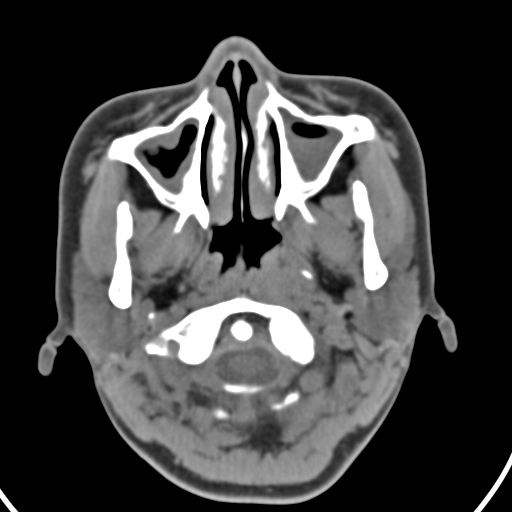

以下是引用zjzjr在2008-12-5 11:46:00的发言:[br]脂肪密度,壁有钙化.考虑口咽部皮样囊肿可能性大.双侧上颌窦炎,双侧下鼻甲粘膜肥厚.增殖腺肥大,扁桃体亦增大,考虑炎性.

以下是引用随光逐影在2008-12-5 18:27:00的发言:[br]1)考虑左侧茎突过长综合征并茎突舌骨韧带囊肿形成突入咽部;左侧咽部慢性炎症。2)鼻咽腺样体肥大。3)双侧扁桃体肿大。4)双侧上颌窦炎。5)双侧下鼻甲粘膜肥厚。